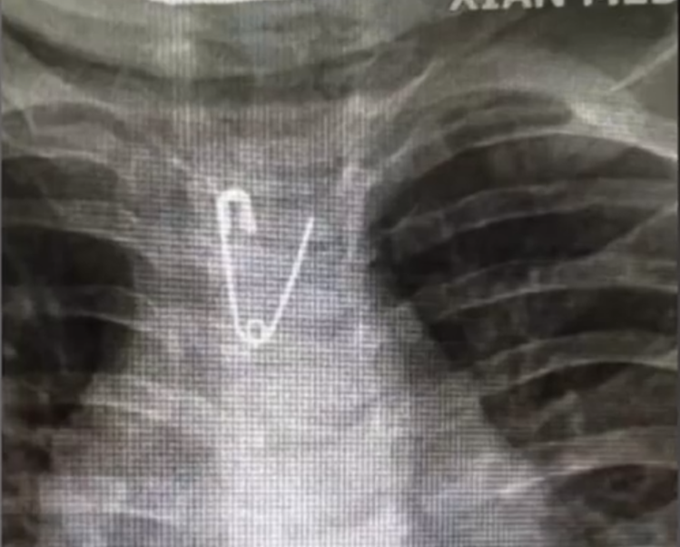

热点太危险!10个月大婴儿误食3厘米长别针,医生5分钟取出

6月12日 , 陕西西安一名刚满10个月的婴儿误食3厘米长别针 , 被紧急送医 , 医生耗时5分钟将别针取出 。 经救治 , 该婴儿状态平稳 。 ![]()

医生称 , 如果送医不及时 , 别针可能会刺破婴儿食管 。 医生提醒家长要看管好孩子 , 把危险物品放在远离孩子的地方 。